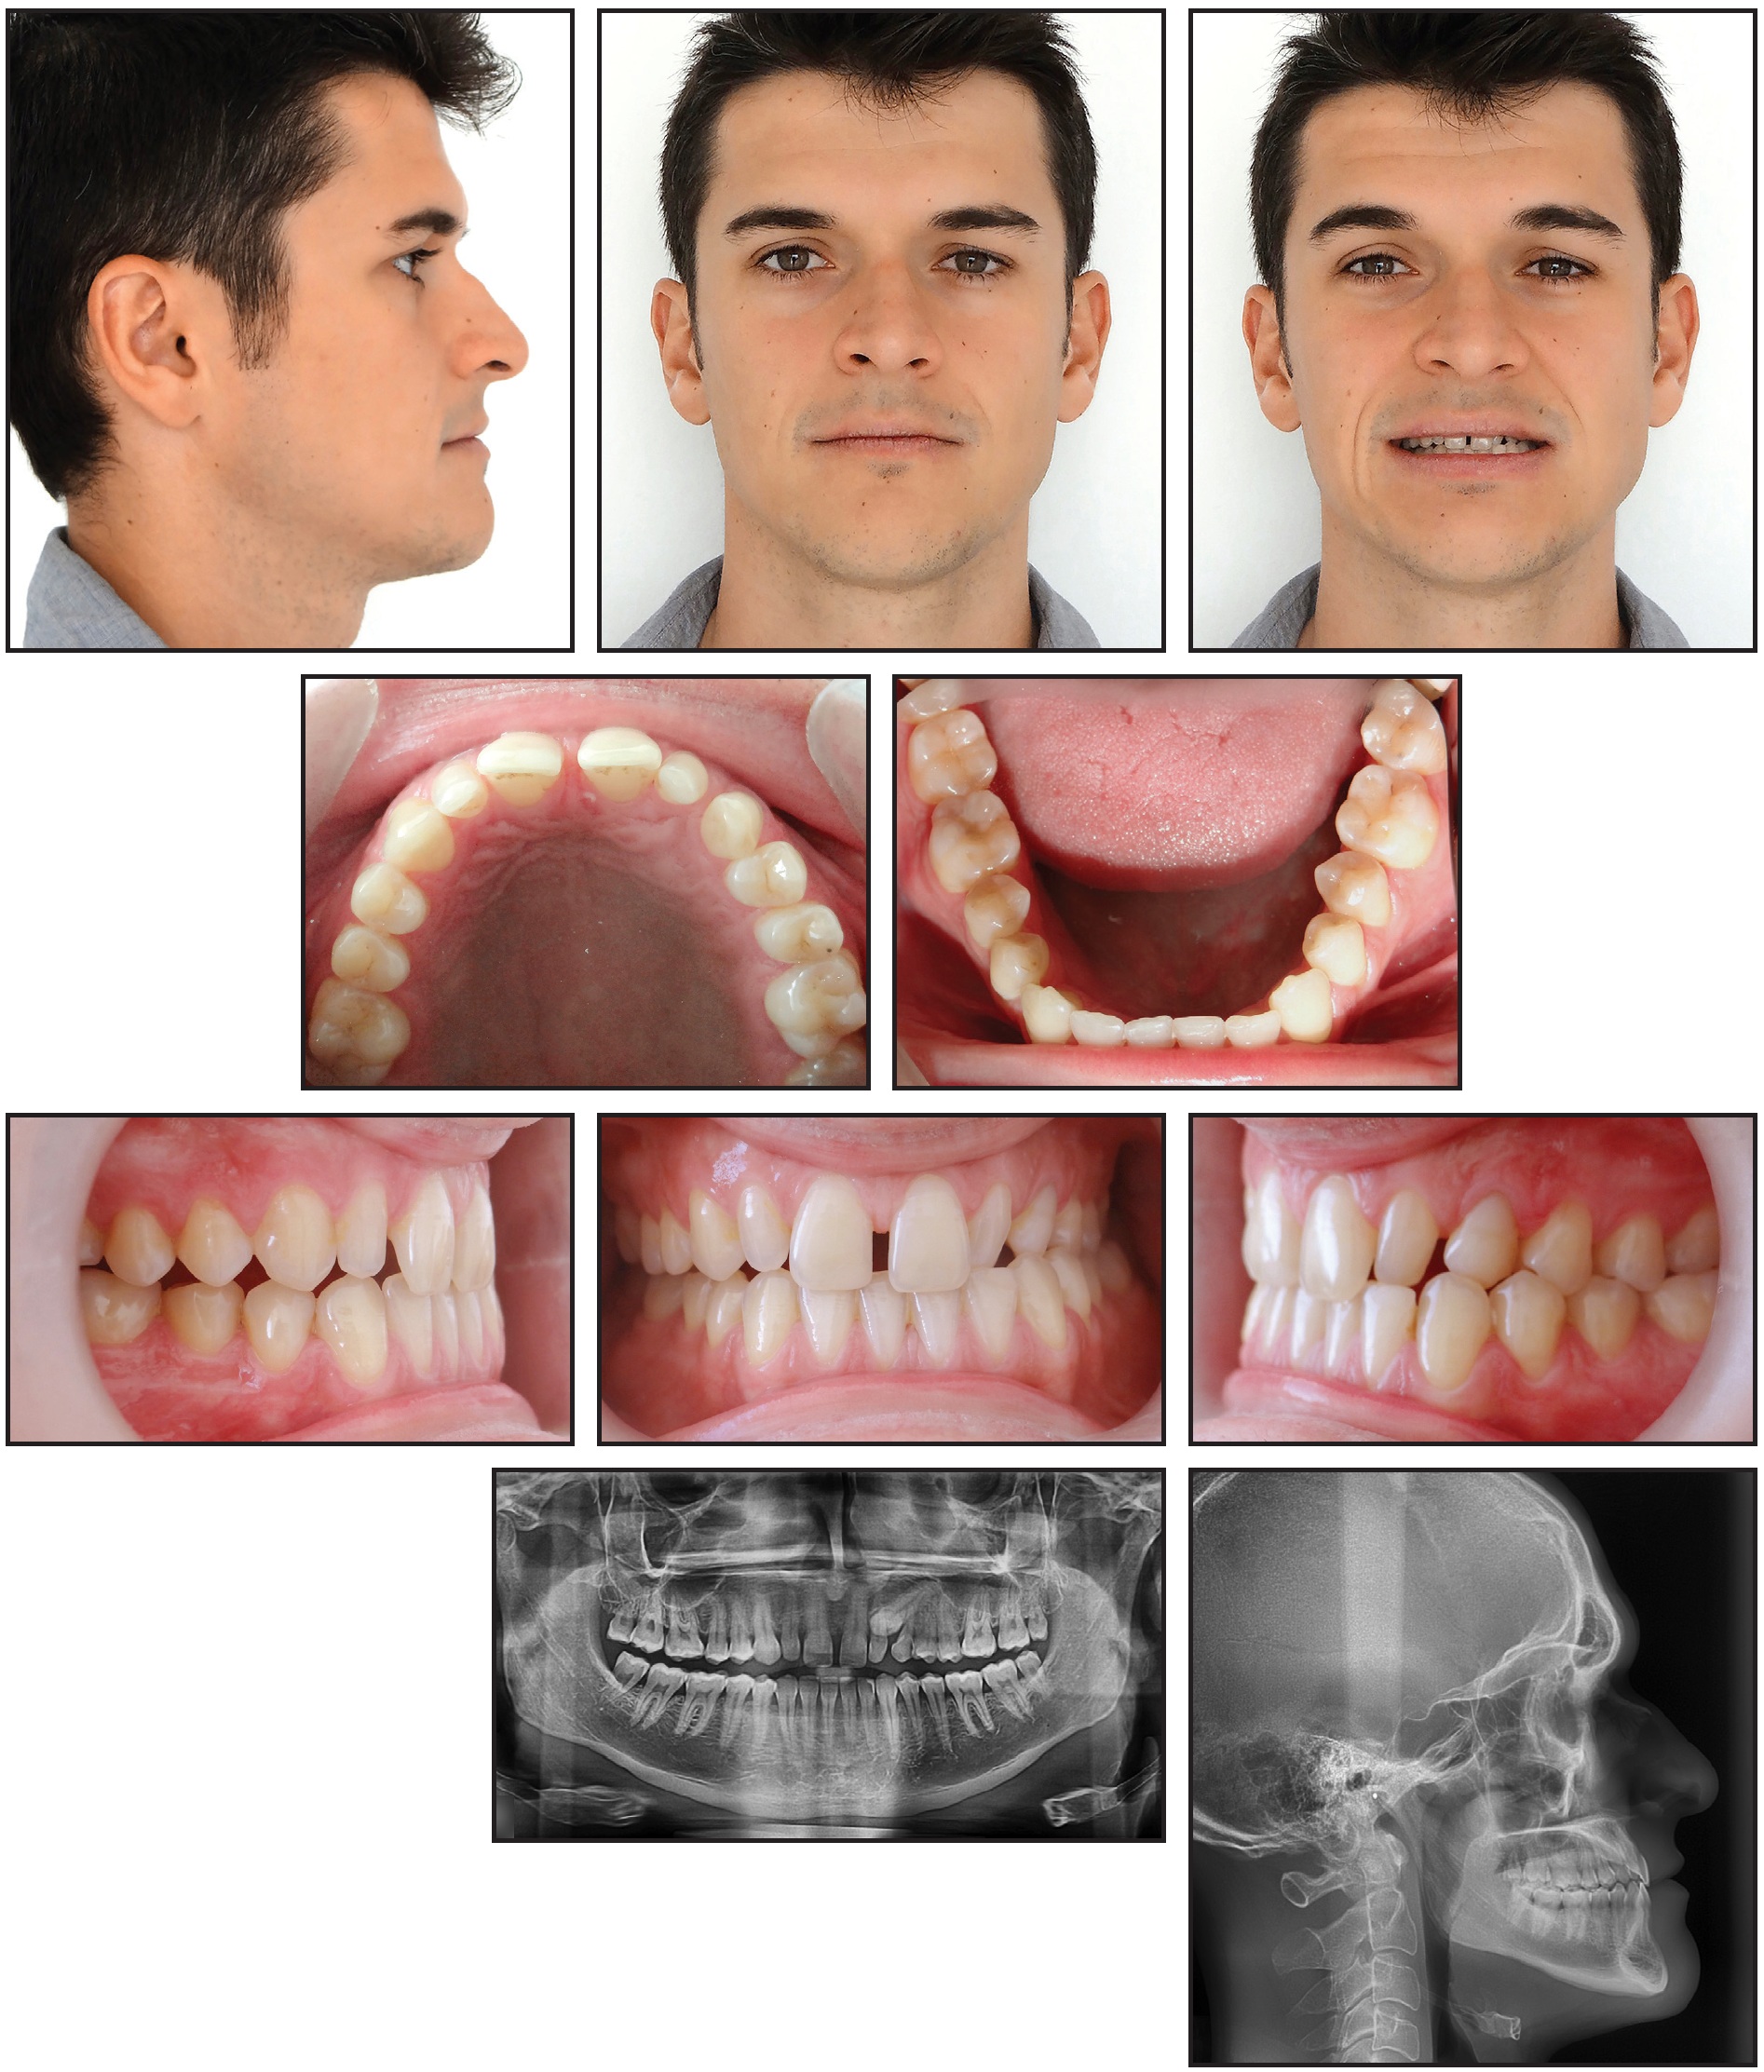

Case 3: Applying Traction Forces with Different Vectors

A 29-year-old male presented with the chief complaint of a gap between his upper front teeth (Fig. 11). The soft-tissue profile was straight, with mildly retrusive upper and lower lips, 50% incisor display in smiling, and a flat smile arc. The mandibular midline was deviated 3mm to the left of the facial midline, and there was a 2mm diastema between the upper central incisors; the overbite was 1-2mm. Class III molar and canine relationships were present on the right side, and Class I relationships on the left. The maxillary arch was constricted compared to the mandibular arch, with a crossbite from the left canine to the left second molar. The lower left deciduous canine was retained, and mild crowding was noted in the mandibular arch. The upper right lateral incisor was in an edge-to-edge relationship with the lower right canine, while the upper left incisor was in an anterior crossbite. Bolton analysis indicated a 2.07mm mandibular excess due to the narrow mesiodistal width of the upper lateral incisors (6mm each).

Fig. 11 Case 3. 29-year-old male patient with horizontally impacted upper left canine, diastema between upper central incisors, Class III molar and canine relationships on right side, left buccal crossbite, and Bolton discrepancy before treatment.

The panoramic radiograph revealed that the upper left canine was horizontally impacted, overlapping the root of the upper left lateral incisor. Cephalometric analysis indicated a Class III skeletal relationship (ANB = –1°, Wits appraisal = –3mm) with a normal vertical dimension (MPA = 34°). Both the upper and lower incisors were retroclined.

Treatment objectives were to bring the impacted canine into the arch and obtain Class I molar and canine relationships, along with a normal overjet and overbite. The Bolton discrepancy would be addressed with porcelain veneers on the upper lateral incisors. The goals of clear aligner treatment (see box) were to expand the maxillary arch, procline the incisors, close the space between the upper central incisors, prepare space in the arch for the impacted canine, and correct the Class III relationship and midline deviation, using Class III elastics for bite stimulation (Fig. 12).

Fig. 12 Case 3. ClinCheck superimposition of initial (white) and planned (purple) tooth movements for first set of aligners.